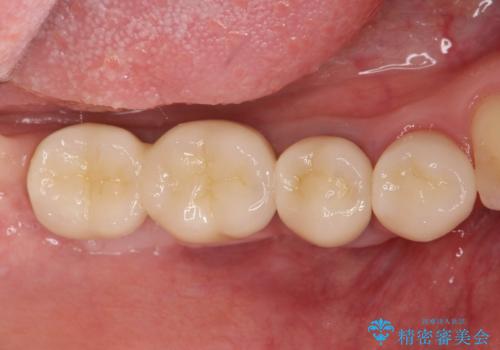

遊離歯肉移植術を伴うインプラント治療

また、機能後のインプラント周囲の清掃性を高めるため遊離歯肉移植術を行っています。

- 110万円(インプラント×2・チタンカスタムアバットメント×2・ジルコニアクラウン×2・仮歯×2・遊離歯肉移植術)費用は治療当時の料金となります

遊離歯肉移植術について

インプラント周囲に強固な歯ぐきを移植することで、歯ブラシがしやすくなりインプラント周囲炎対策となります。